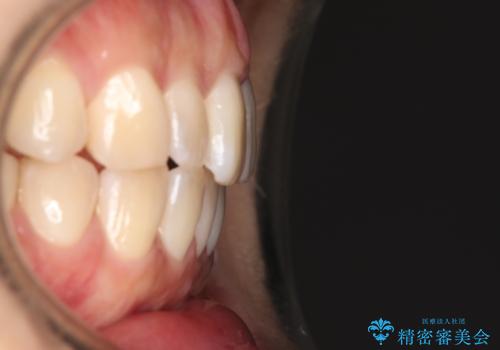

かみ合わせを整えるためにゴム掛けも行いながら、治療していきました。

患者様にマウスピースの使用とゴム掛けを頑張っていただいたおかげでリファイメント(マウスピースの再発注)も1回で終了することができました。